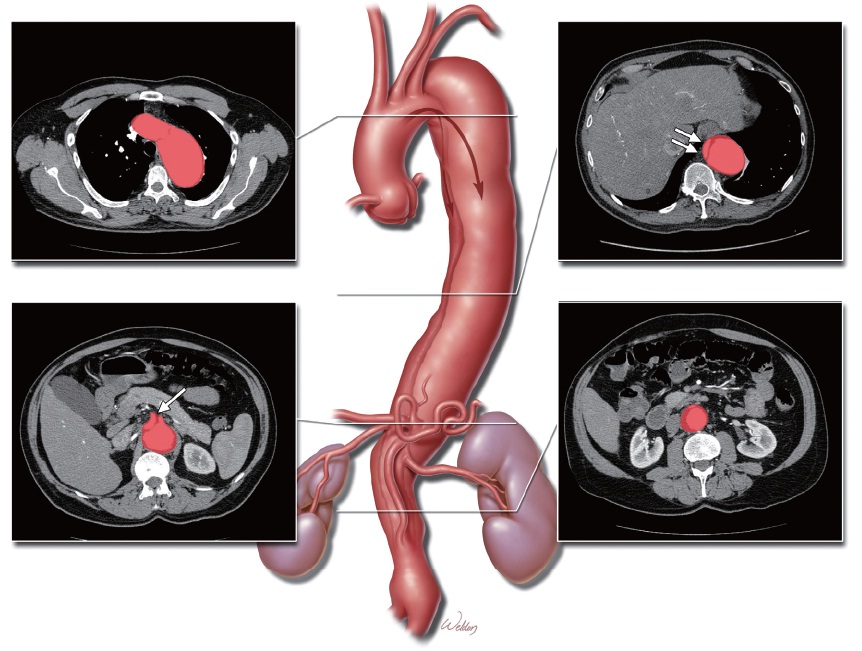

Traumatic infra-renal aortic dissection after a high-energy trauma: a case report of a primary missed diagnosis the abdomen shows the dissection of the infrarenal abdominal aorta. A) Axillary and B) coronary view. Figure 2. ... Read Document